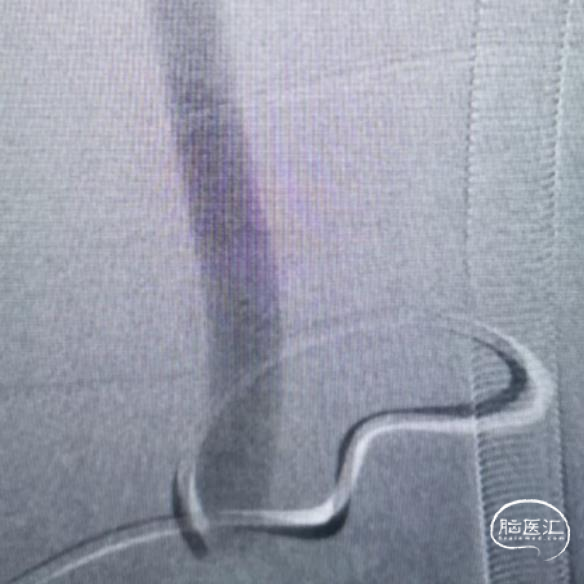

腹主动脉360度弯曲

造影评估

通路建立,治疗狭窄

Xact支架植入

支架形态